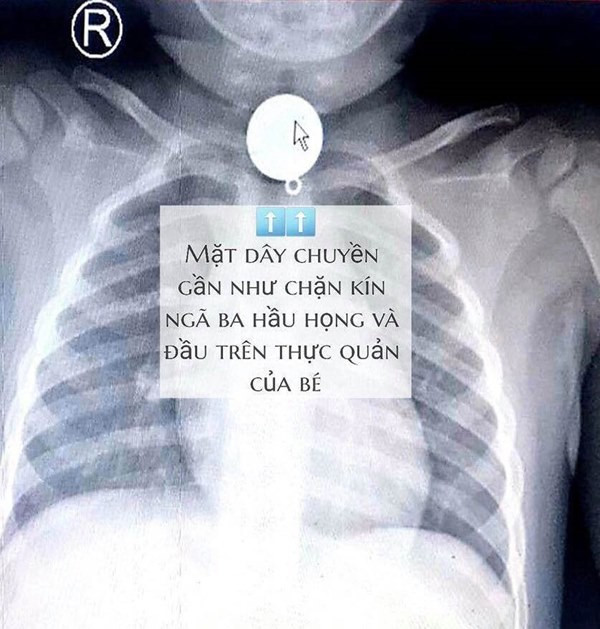

Tại bệnh viện, sau khi hội chẩn xác định dị vật mắc trong cổ bé rất to, hình tròn nằm chiếm hết lòng đầu trên thực quản, gần ngay ngã ba thông với đường thở, các bác sĩ nhận định khả năng dị vật gây trầy, rách thực quản, hay hóc ngược vào đường thở rất cao nếu xử trí không khéo.

| Hình ảnh chụp X-Quang của bé trai. |